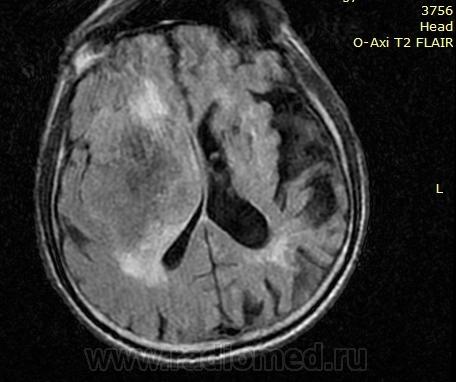

Пациент в тяжелом лежачем состоянии, резкое ухудшение 2 недели назад, прогрессирует. В конце 70годов лечился от туберкулеза легких. С 80гг время от времени наблюдается у невропатолога: нарушение сна, утомляемость, головные боли. На рентгенограммах от 03года выраженные фиброзные изменения, в верхушках множественные очаги (похоже на перенесенный tbs), в корне левого легкого от 10года какая-то не очень ясная маленькая тень/тяж, от 11 года там же большое 5-7 см плотное образование (похоже на центральный рак). И вот такая голова.

Возможно, а о чем Вы думаете? Я к тому, что сброс снимков мне обходится в 4-5 стадий. Расскажите, что ожидаете там увидеть, и что именно Вас смущает? Лично меня -отсутствие выраженного масс-эффекта. На снимках представленных уважаемым Валентином Львовичом патология как-раз таки укладывается в метастатическое поражение. Здесь же- огромный размер,  минимально выраженный перифокальный отек от сдавления, а на представленных сканах срединная линия вообще не смещена. Ниже она уходит влево до 5 мм. Сказать куда подевался весь объем, если это мтс- затрудняюсь. Разве что в расширенную на фоне атрофии сильвиевую щель, если она была такая же, как слева. Отсюда и возникли сомнения, а не туберкулема ли это с расплавленным веществом г.м. внутри. Да и контраст как-то вяленко идет, не по-злому.

По мне выглядит как опухоль, на Т2 туберкулезные дела дали гиперинтенсивный сигнал, однако для полной уверенности надо провести диффузно-взвешенную последовательность, если усиление сигнала будет только по периферии или вообще нет усиления то вероятнее всего опухоль, если усиление сигнала по всему образованию то уж точно воспалительный процесс (tbc?), что врядли...

Во-первых сразу же смущает диф.ряд “mts, tbc”. Слишком редко встречается единичный метастаз или туберкулезное поражение ГМ таких больших размеров.

Во-вторых несоизмеримость размеров поражения и выраженности перифокальной реакции. Как метастатическое поражение так и туберкулезное, да еще таких размеров, должны сопровождаться выраженным отеком. Далее о самой перифокальной реакции. Вы полагаете, что это «отек»? Но учитывая столь незначительную выраженность реакции, не формирующейся ли это перитумарозный глиоз от длительной компрессий мозговой ткани.

В-третьих туберкулезное поражение ГМ проявляется в двух формах: это туберкулезный менингит, что мы сразу исключаем, и туберкулома – инкапсулированный очаг казеозного некроза. Туберкулома имеет довольно толстую капсулу и гораздо более неоднородную структуру, чем на представленных снимках. Кстати и для mts-поражения характерна более гиперинтенсивная структура по Т2 ВИ. Теперь о накоплении К/В: в случаи с туберкуломой это должно быть кольцевидное контрастирование, т.е накопление идет по капсуле (сам некроз копить контраст не может!!!!!!!), для метастазов характерен и кольцивидный тип накопления и диффузный. Ни тот ни другой вразумительно в данном случаи не прослеживается.

Далее, такие мелочи, как гистологическая верификация объемного образования легких. Была ли она? Если да, то каковы её результаты? Если Сr тогда вопрос снимается с повестки дня. Если нет, до при длительном туберкулезном анамнезе, лимфогенное распространение процесса приводит к вовлечению бифуркационных, паратрахеальных и шейных лимфоузлов.

Исходя из этого меня интересуюсь нет ли связи образования с ТМО в конвекситальных отделах либо в области основания? Если таковая отсутствует, то вариант оболочечного поражения снимается. Но диффиренциальный ряд «mts, tbc?» лично для меня под большим вопросом.